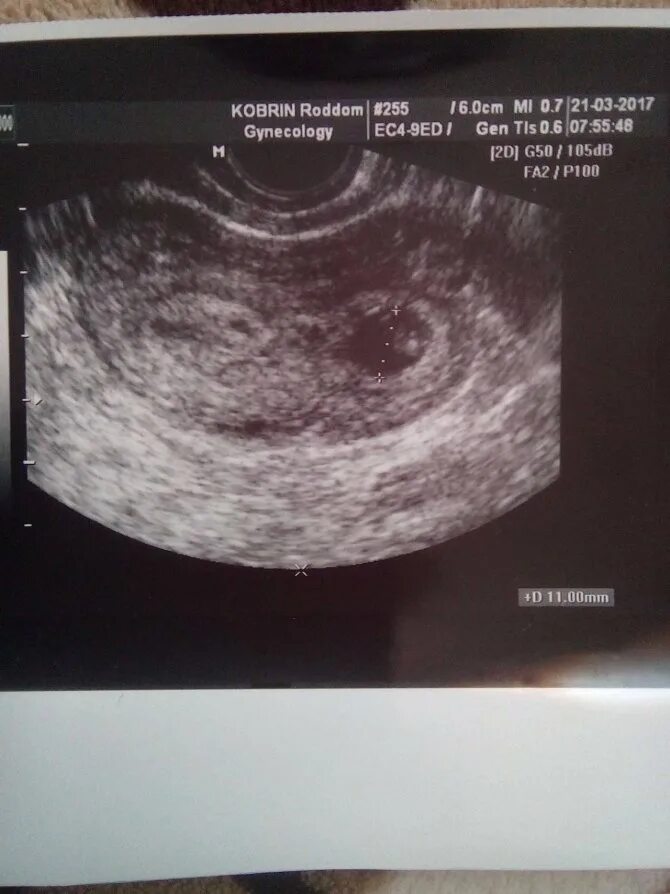

Плодном яйце не визуализируется эмбрион